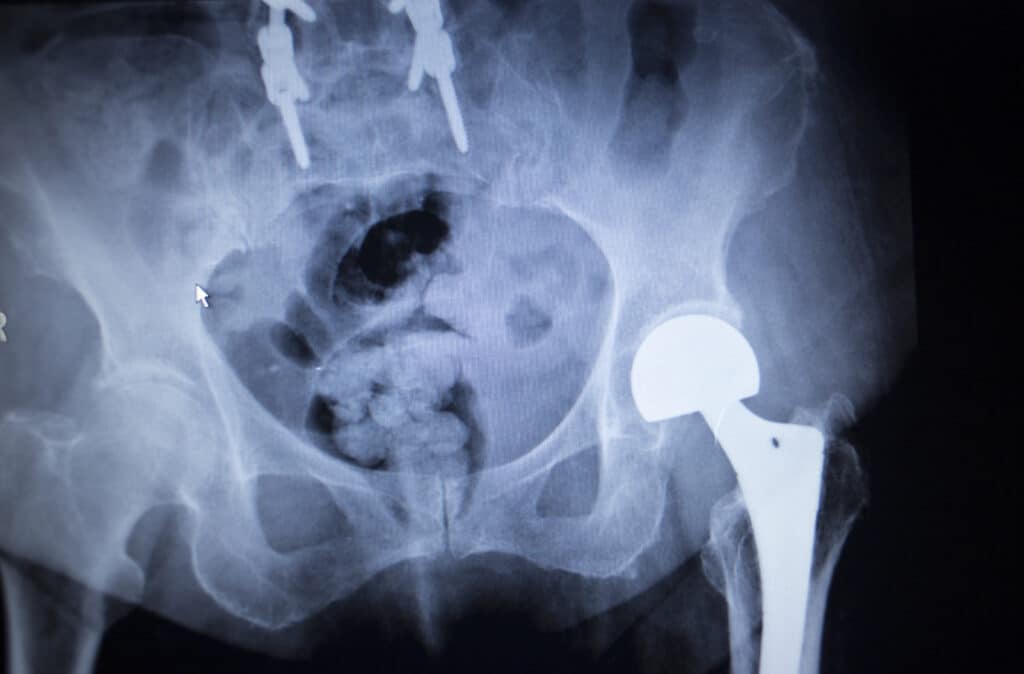

Study: Do the hip first

A March 2024 study (15) sought to add input into the “increasing debate among orthopaedic surgeons over the temporal relationship between lumbar spinal fusion and total hip replacement for patients with hip-spine syndrome.” The researchers noted “few large studies have directly compared the results of patients who undergo lumbar spinal fusion prior to total hip replacement to those who undergo lumbar spinal fusion after total hip arthroplasty.” In a study of 716,000 patients. The researchers found lumbar spinal fusion first patients experienced significantly more postoperative dislocations at 90 days and 1 year compared to hip replacement patients. There were a similar number of revisions performed for spine first and hip first surgery patients at both 90 days and 1 year. At one year, lumbar spinal fusion first patients experienced more pneumonia and joint infection.

The option to have lumbar spinal surgery and hip replacement at the same time is clearly one that is not recommended for obvious reasons. So a decision has to be made. Spinal surgery or hip replacement surgery? One has to come first and one has to wait.

Because you cannot do a spinal surgery and a hip replacement at the same time the patient and their surgeons need to pick the one that helps the most. If you went to your hip surgeon, he/she may recommend the hip first, if you went to your spinal surgeon he/she may recommend spinal surgery first. So you have 2 different “first surgery,” recommendations. Sometimes, there is agreement, sometimes there is conflicting opinions.

A June 2019 published in the Bone and joint journal (6) suggests controversy in the decision making process of the patient with hip and spinal degenerative disease. Here is what the surgeons are struggling with.

- Patients who are being recommended to both hip replacement and lumbar spinal surgery have to make a choice which surgery to do first. Recommendations from their surgeons as to which surgery should be performed first remain uncertain and can confuse the patient.